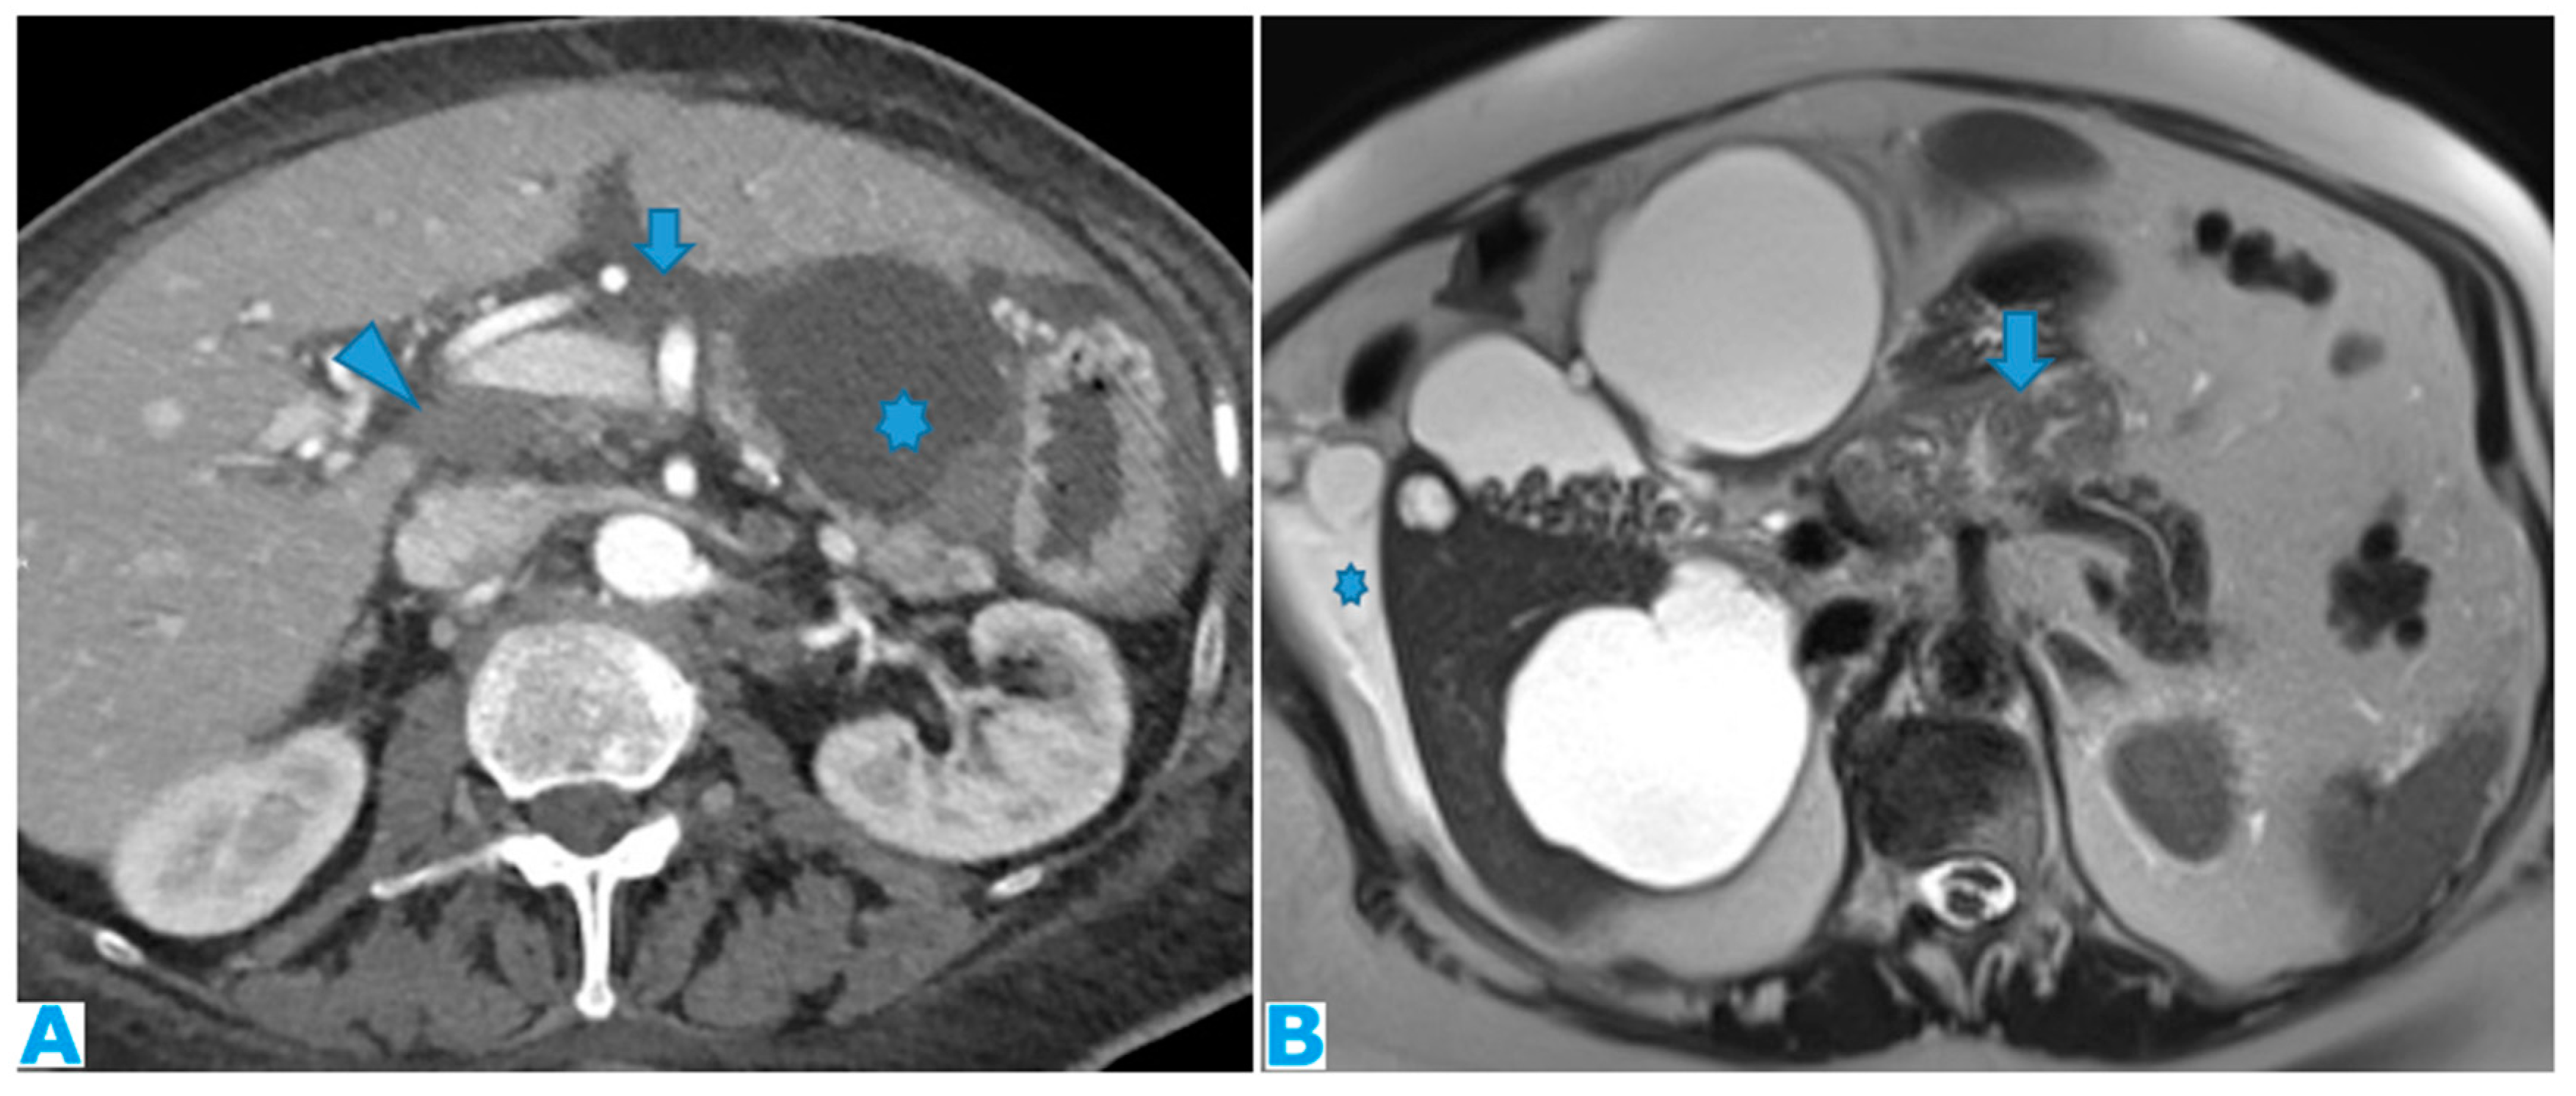

Figure 15.

Axial CE-CT (A). PC from ovarian carcinoma: mass-like deposit within the lesser sac (*). Also notice the seeding within the lesser omentum (arrow). Portacaval lymph node (arrowhead). Axial T2WI (B). PC from ovarian carcinoma: mass-like deposit within the lesser sac (arrow). Ascites (*).